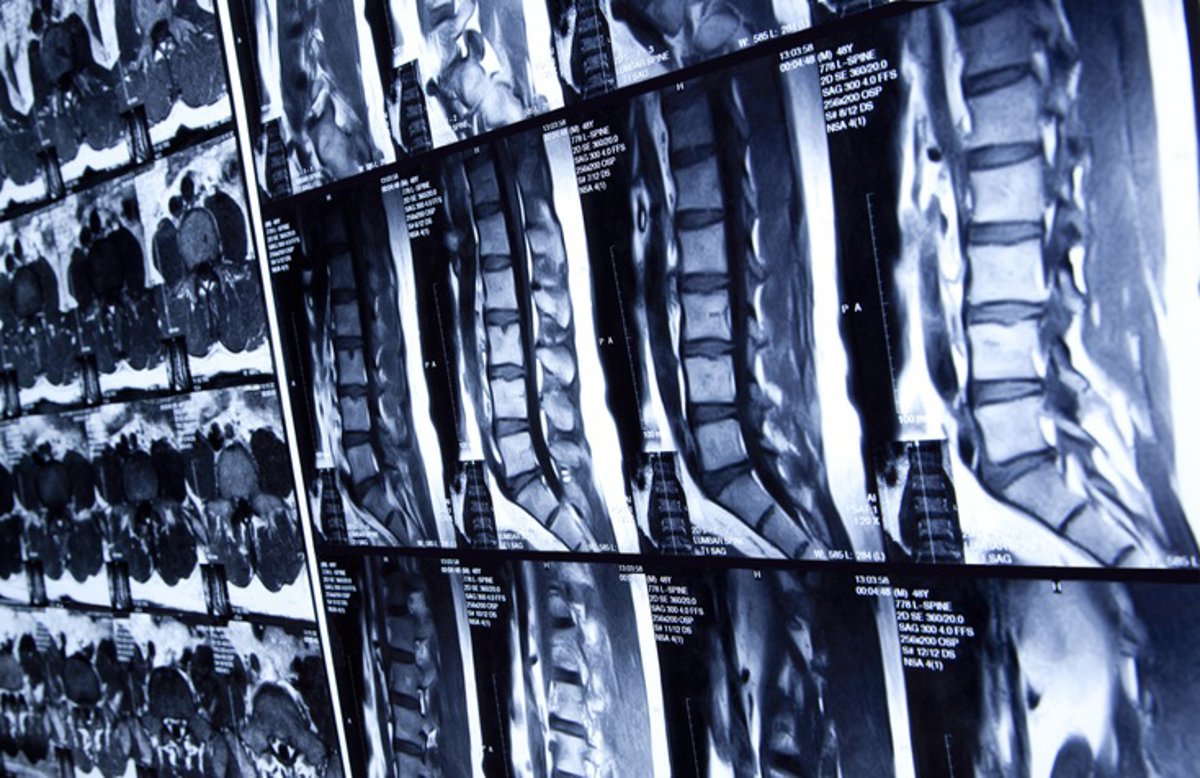

Archivo - Médula espinal

Archivo - Médula espinal - HADELPRODUCTIONS/ ISTOCK - Archivo